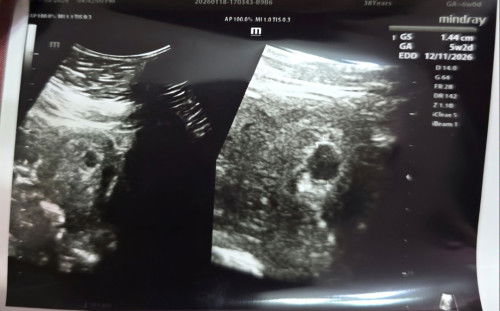

21 weeks now